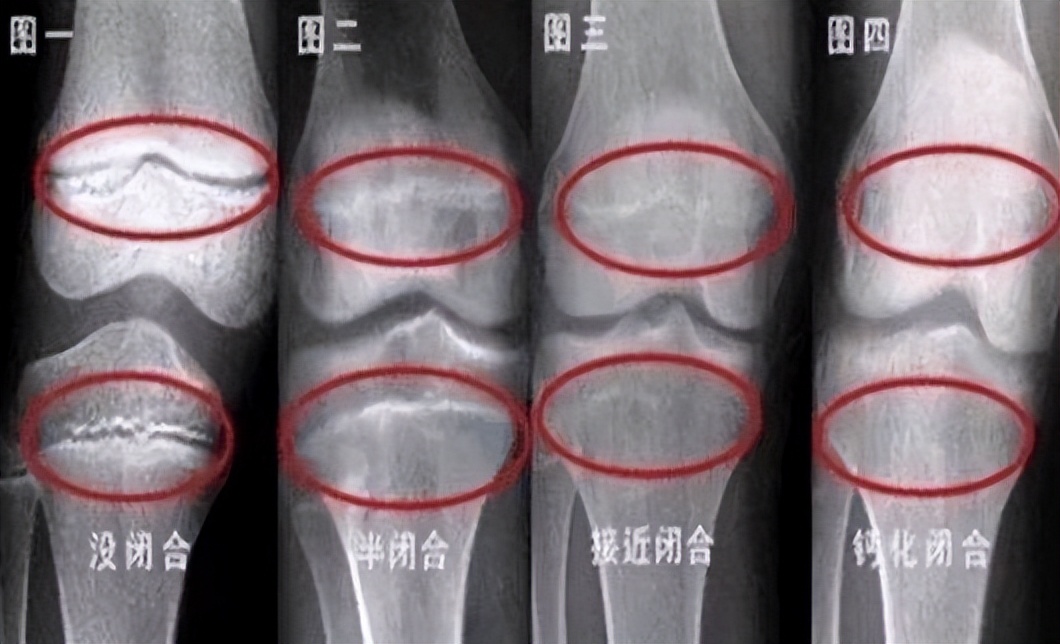

原因就是,补钙确实有可能帮助孩子长高,但是,如果孩子本身就不缺钙,还一直给孩子补钙,就很有可能会导致孩子骨垢线提前闭合,以后就不会再长高了。

奶奶说,医生告诉她,孩子到18岁骨骺线就闭合了,长高黄金期真的不长,希望家长们要重视起来,不要让孩子“矮人一等”。